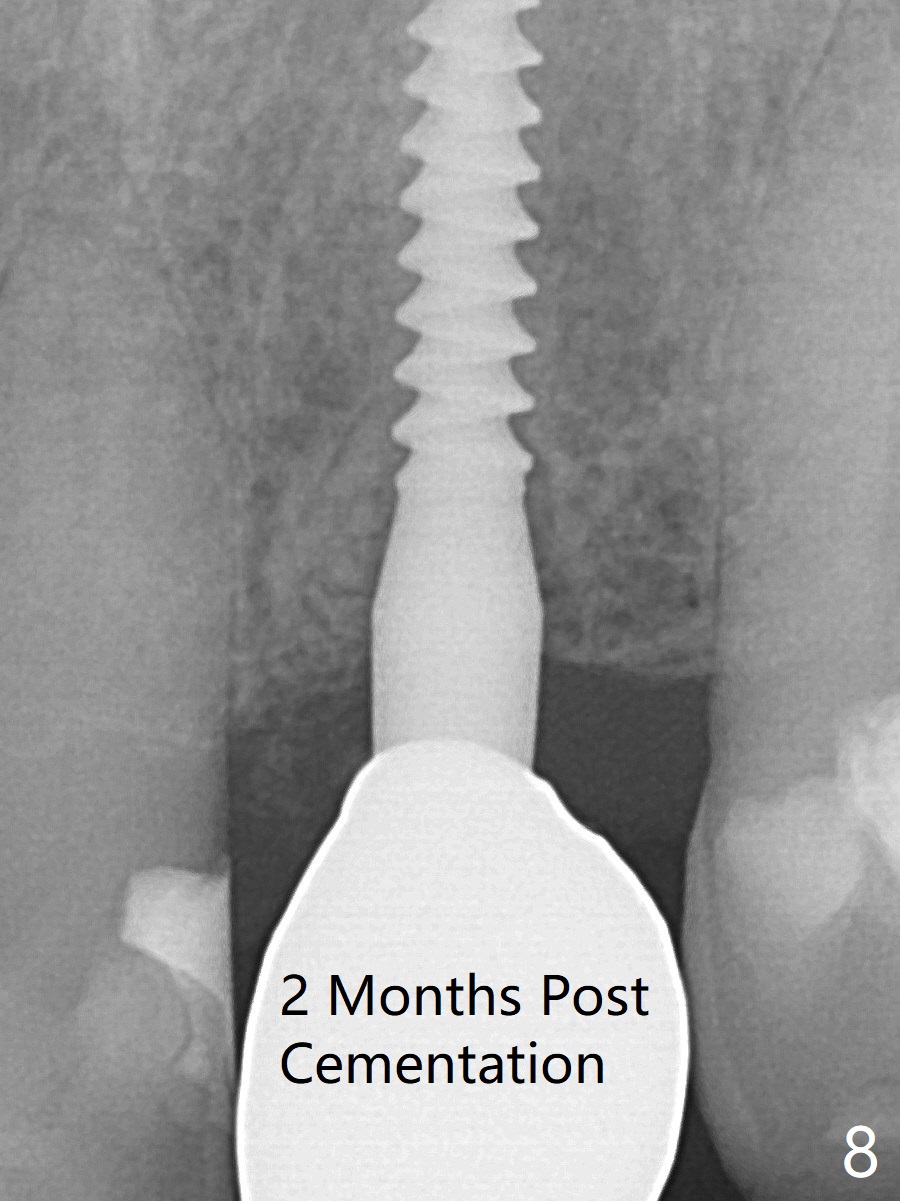

After undersized drilling in depth at #10 (2.2x13 mm (10.5 mm offset), Fig.1), a 2.5x13 mm 1-piece implant is placed (Fig.2,3), as compared to the design (Fig.3'). Following 3 more turns of the implant (~ 20 Ncm), bone graft and heavy buccal reduction of the coronal end of the abutment, an immediate provisional is bonded to the tooth #9 (Fig.4) and splinted to the tooth #11 with a twisted wire (Fig.5). To increase stability and reduce reduction, a 3 mm 1-piece implant could be used with 15 degree abutment. The implant remains stable 5 months postop (Fig.6). The implant seems to be flexible before heavy occlusal reduction; note the periimplant micro-space (Fig.7). The patient is a bruxer. The implant crown seems to be minimally mobile 2 months post cementation (Fig.8, without treatment). 牙冠粘固后1年1个月软硬组织正常(图九)。